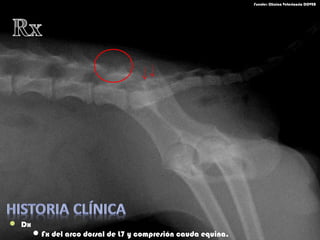

 Dx

 Fx del arco dorsal de L7

Fx del arco dorsal de L7 y compresión cauda equina.